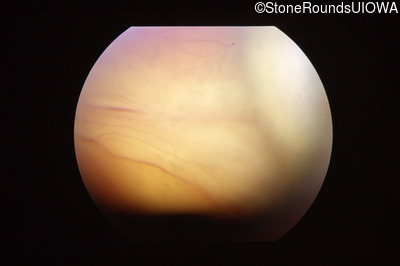

Visit at age: 35 months

Fundus Photography - Right - Light Perception

Exemplar